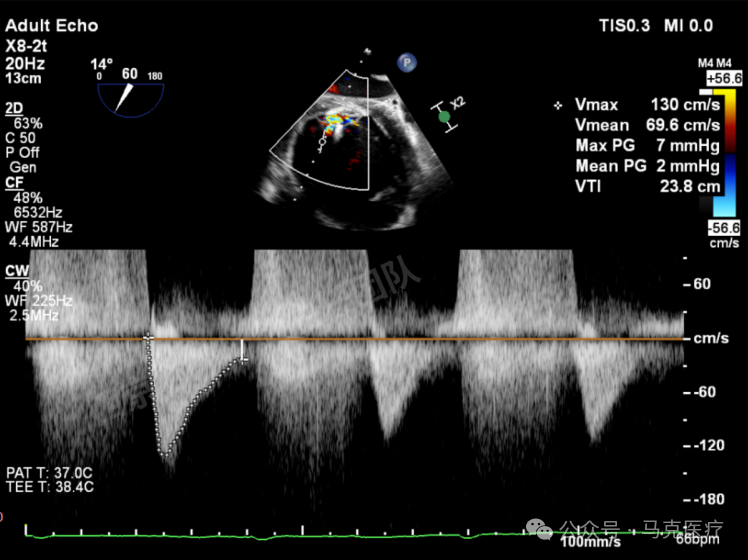

第二枚XT关闭后评估,trace

图片

二尖瓣平均跨瓣压差1mmHg